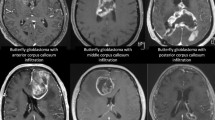

Region of interest (ROI) selection was performed using an in-house developed program written in MATLAB (Math Works, Natick, MA). Two trained reviewers (NSP and JY) independently selected hypointense foci that were not contiguous with perpendicular blood vessels, flow voids or consistent with mineralization (calcification). During this analysis, small focal intracerebral hemorrhages only visible on susceptibility sensitive MRI sequences (cerebral microbleeds) and Zabramski cavernoma classification Type IV malformations were not differentiated as they are radiographically indistinguishable at 3 T and both are associated with radiation related small vessel abnormalities30,31. Selection of microbleeds was confirmed by a board certified neuroradiologist. All coding was conducted without knowledge of treatment exposure or neurocognitive function.

Each microbleed was segmented using a 2D recursive region growing algorithm from a seed indicated by an experienced observer (Fig. 1). The connected 2D segments were combined to generate a 3D segmentation of the microbleeds. For each microbleed, the location of the center of mass and size in voxels and mm’s was recorded, as well as the microbleed count for each individual survivor. The coordinates for the center of mass of each microbleed were transformed into a standard brain reference space (MNI space) by first normalizing the SWI data set into template space using Statistical Parametric Mapping v12 (SPM 12)32. The resulting transformation was then applied to the coordinates of the center of mass. The coordinates were then mapped to Talirach space using the icbm2tal transform technique as previously described33. Location labels were generated for each microbleed based on the coordinates of the center of mass using the taxonomy maps developed by Brainmap.org.34,35. Microbleeds were assigned to one of the following locations: frontal lobe, parietal lobe, temporal lobe, occipital lobe, anterior lobe cerebellum, posterior lobe cerebellum, medulla oblongata, pons, sub-lobar (region defined to fill the remainder of volume within the hemisphere, such as the insular cortex) and midbrain. Locations were combined for left and right side. Additionally, microbleeds were categorized as located in grey matter or white matter, unless in the sub-lobar and brainstem regions where they were classified as mixed.

Example of a region of interest selection performed by the region filling algorithm. The arrow highlights the same microbleed in both the Susceptibility Weighted Minimum Intensity Projection image (SW mIP) (A,C) and corresponding Filtered Phase image. (B,D) Note detection and measurements could be accurately captured near areas of air induced susceptibility artifacts (orange arrow) using this method. (C,D) (Images are displayed in radiological convention).